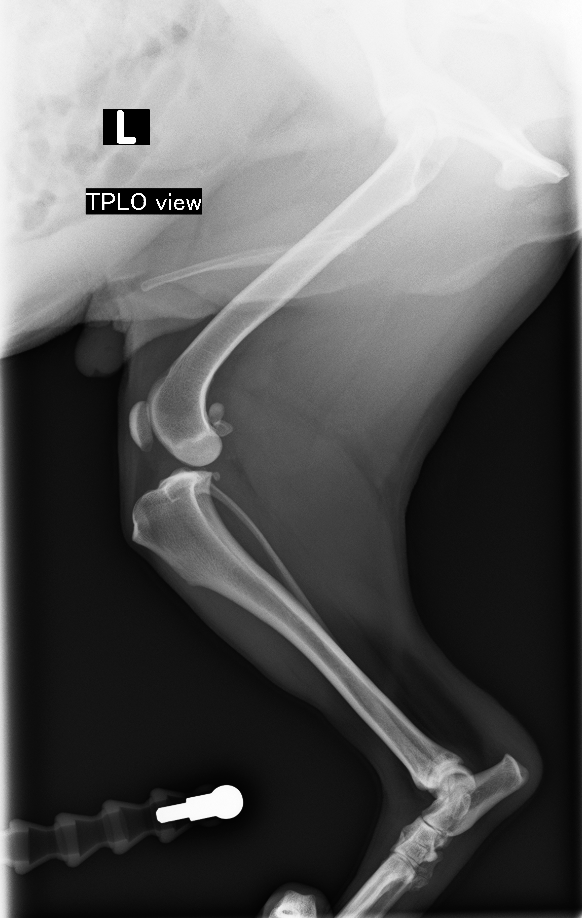

触診、レントゲン検査より、脛骨の前方変移、TPA(Tibial Plateau Angle 脛骨高平部の角度)32°が認められた

TPLO(脛骨高平部水平化骨切り術)